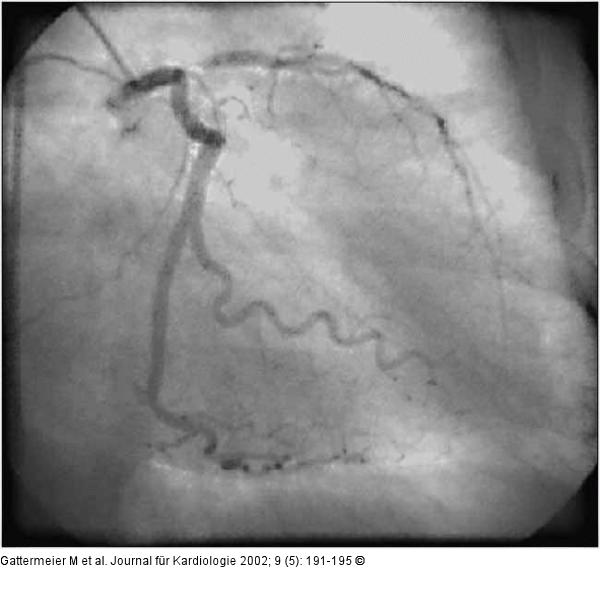

Abbildung 2: Subakute Stentthrombose - Fallbericht Subtotaler LAD-Verschluß am Abgang, Projektion von rechts-kaudal. |

Abbildung 2: Subakute Stentthrombose - Fallbericht

Subtotaler LAD-Verschluß am Abgang, Projektion von rechts-kaudal. |